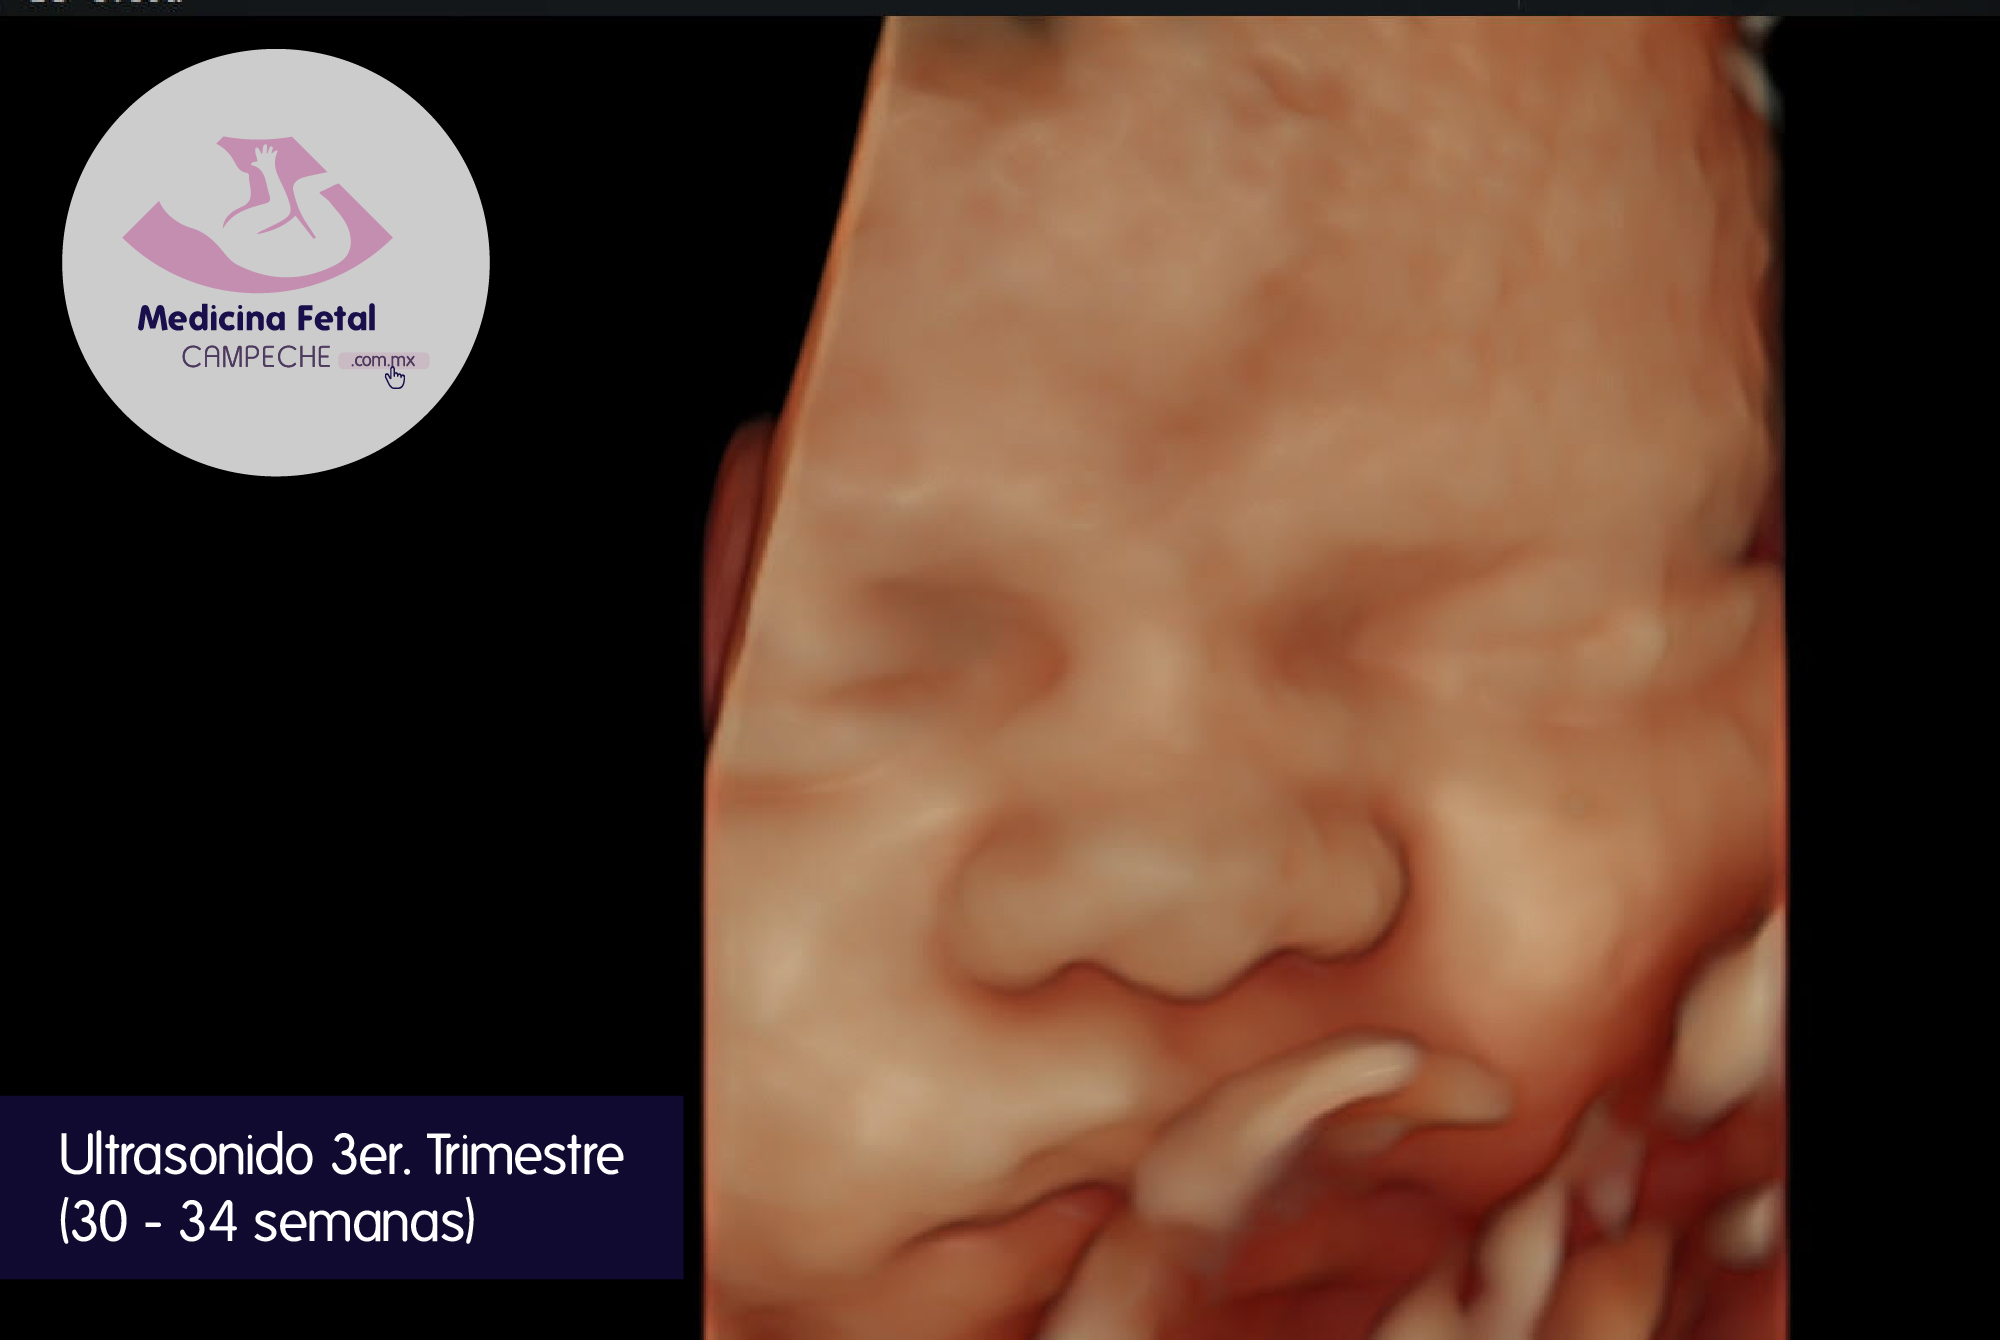

Revaloramos la anatomía fetal, porque es importante mencionarte que algunas anormalidades como las de tubo digestivo y aparato urinario se manifiestan hasta el tercer trimestre.

Evaluamos el patrón de crecimiento: es decir que el peso y crecimiento de tu bebé correspondan a las semanas del embarazo.

Completamos la evaluación anatómica con mediciones de parámetros Doppler de la circulación en estructuras importantes como cordón umbilical, circulación cerebral y circulación de arterias uterinas (vasos que llevan la sangre al útero o matriz).